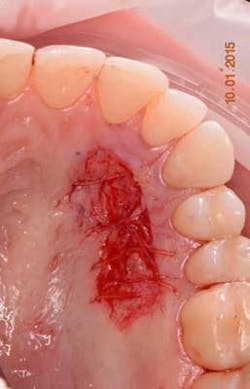

The following will now describe the free gingival autograft surgery that was used to augment the zone of keratinized tissue prior to orthodontic therapy. Three carpules of 3% Septocaine (Septodont, 1.7 ml carpule) was used as a local anesthetic for both infiltration of the donor palate area and inferior alveolar/mental nerve block of the recipient site. Injecting local anesthetic in the mucosa of the recipient site helps to identify the MGJ (mucogingival junction). A submarginal, split-thickness incision with a 15 blade was used to prepare the recipient site. Using aluminum foil to measure the amount of graft needed (figure 3), a full-thickness, free gingival graft was harvested from the upper right palate in the area of Nos. 3-6. Careful attention is paid not to harvest the site too anteriorly to avoid ruggae as well as limit increased post-operative pain.

The harvesting technique (figure 4) should aim for a graft thickness between 1-3 mm and be 15-25% larger than the desired final size. Harvesting a larger amount of graft is warranted due to both initial (immediate) and secondary contraction of the graft during healing. A thin graft will have less primary and more secondary contraction, where as a thick gingival graft will have more primary and less secondary contraction. In general, a harvested soft-tissue graft can be expected to shrink on average of 15% to 20%.